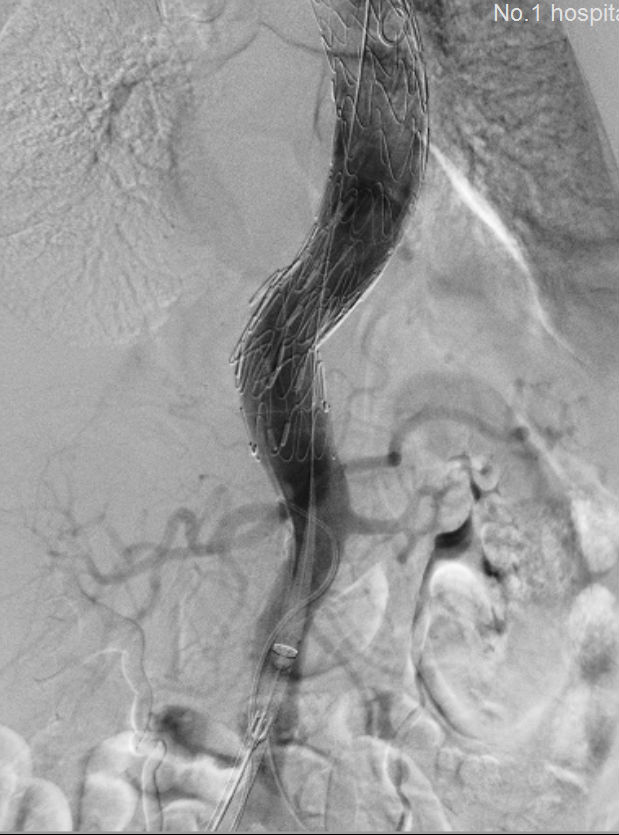

术前 术后